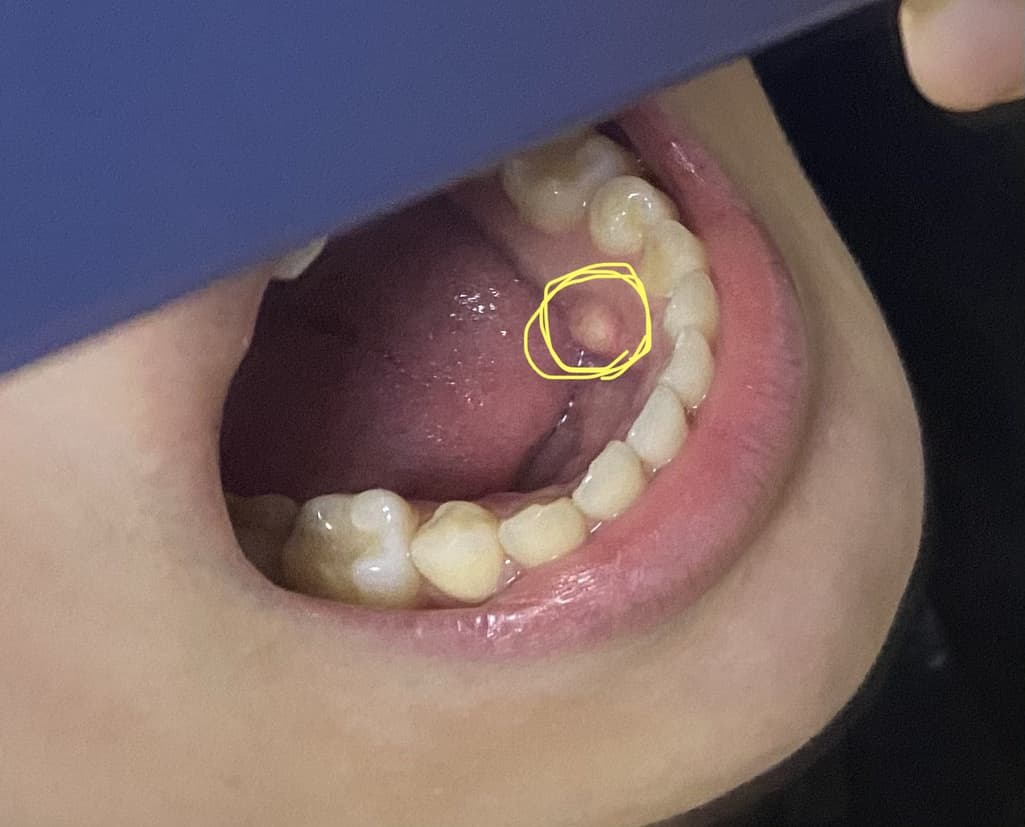

아랫니 안쪽 잇몸에 저 노란색으로 된 쪽에...

꼭 숨겨둔 이가 있는것처럼 잇몸이 튀어나와있어요.

안에 있는게 진짜 치아인듯 딱딱한것 같구요...

질문하신 내용에 대하여 아래와 같이 답변 드립니다.구강의 정상구조물인 torus입니다.

정상적으로 뼈가 돌출된 부분이며, 크기가 엄청 크신분들도 간혹 존재합니다.

병적 요인이 아니고 정상구조물이기 때문에 놔둬도 되지만, 너무 torus가 큰분들이 불편함을 호소하시면 torus를 어느정도 삭제하는 수술을 진행하기도 합니다.

질문하신 내용에 대하여 아래와 같이 답변 드립니다.사진으로 봤을 땐, 외골증일 가능성이 높습니다.

외골증의 경우, 보통 아래 4,5번째 치아의 혀쪽 잇몸뼈에서 생기고, 보통 별 문제는 없습니다.

보통 나이가 들면서 커지는 경향이 있습니다.

만약, 크기가 급격히 커지거나 통증의 증상이 있다면 치과에서 검진을 받아보시길 권해드립니다.